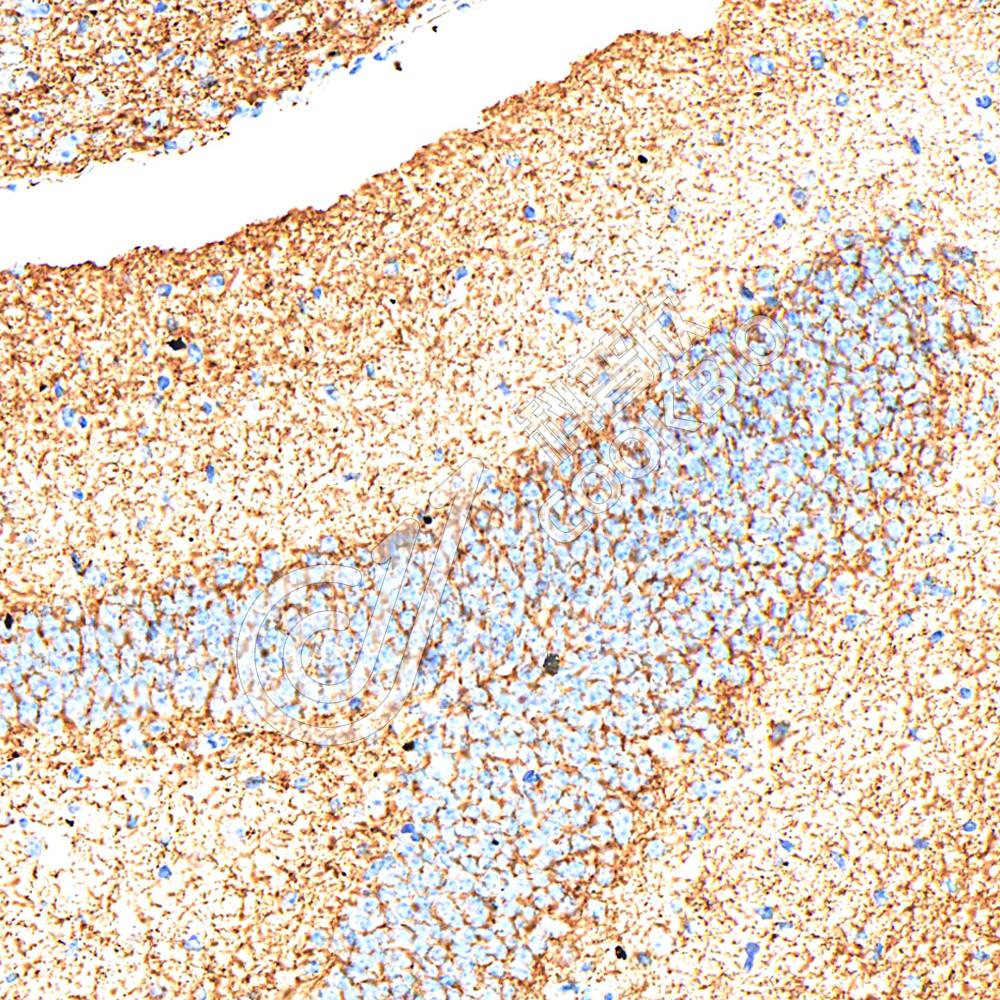

IHC检测GAD65蛋白(货号 K546686).

样品: 大鼠海马区, 4%多聚甲醛 (货号KSG1101) 固定12-24小时.

抗原修复: Tris-EDTA抗原修复液(pH 9.0) (KSG1203), 98℃, 20分钟.

—抗: 1: 1500稀释, 4℃ 孵育过夜.

二抗: S-vision免疫组化多聚二抗(山羊抗小鼠), 即用型(货号KB3903), 室温孵育20分钟.